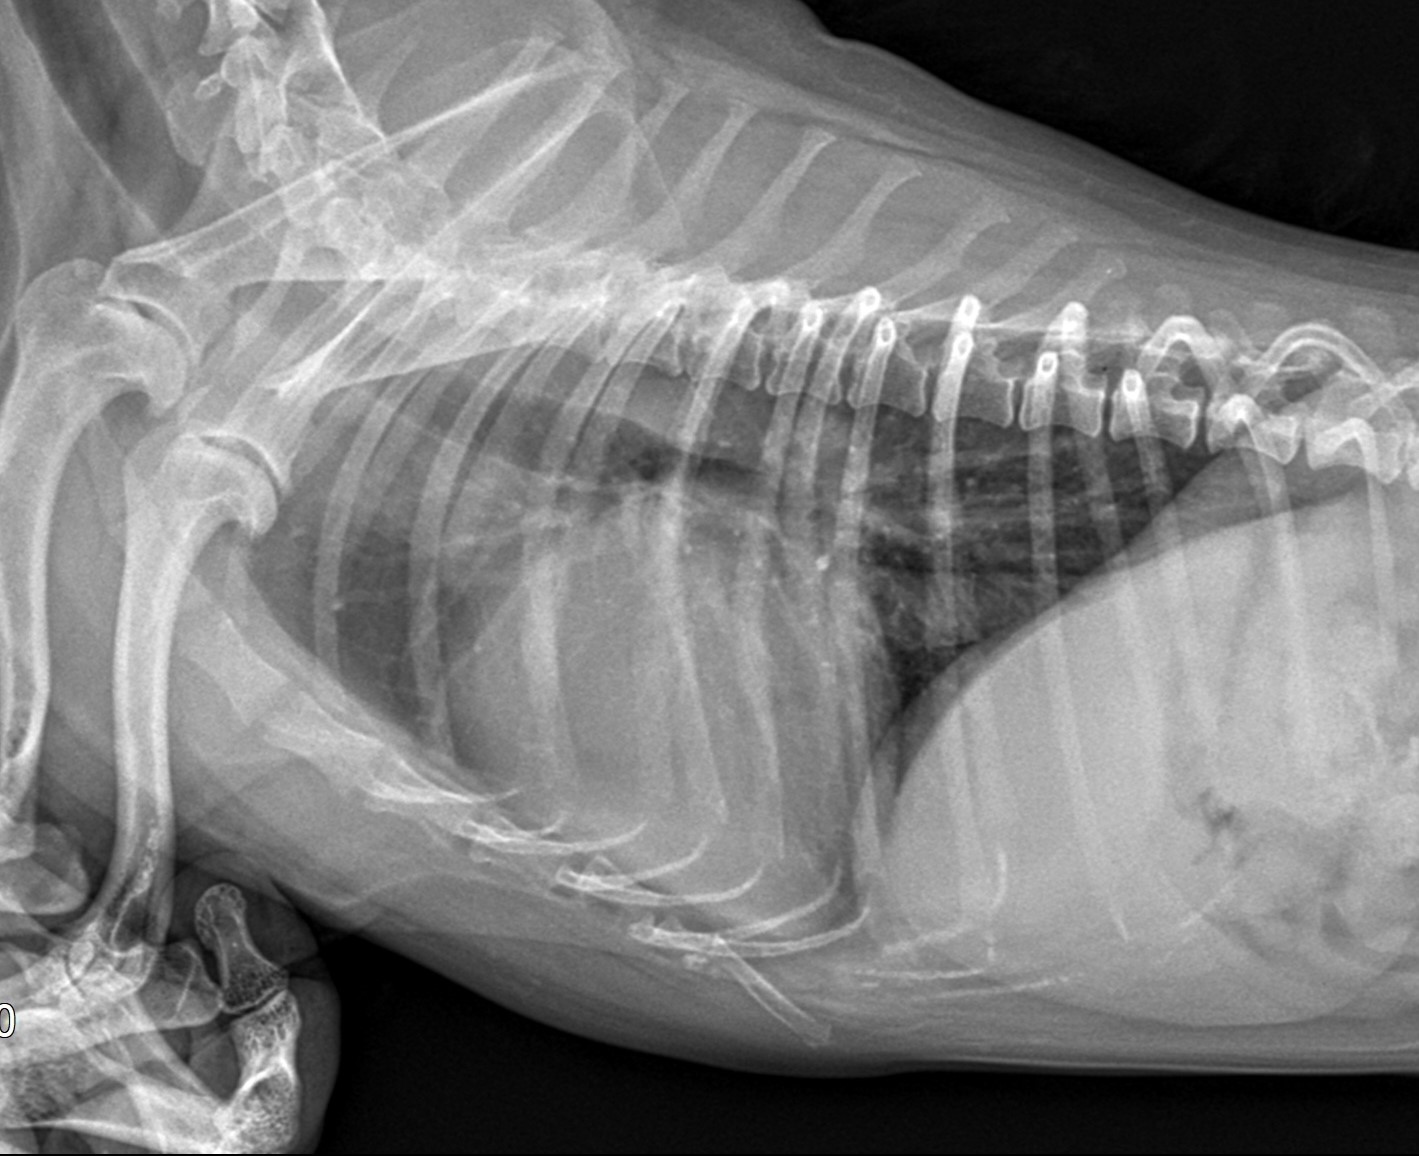

X-ray 촬영

흉부 방사선 촬영을 통해 기관의 굵기, 형태, 이상 유무를 판단한다.